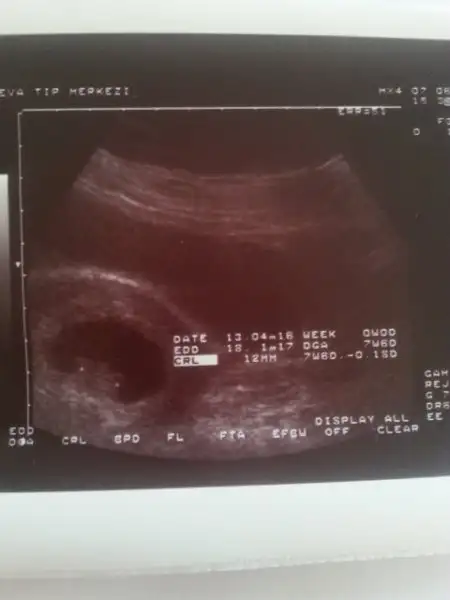

Bana da yorum yapar mısınız? 8 ve 12.haftaları yüklüyorum .karından usg bu arada.Bence keseye gore kiz gibi rabbim gonlune gore nasip etsin insallah

Kiza benzettim tabi rabbim bilir rabbim gonlune gore nasip etsin insallahBana da yorum yapar mısınız? 8 ve 12.haftaları yüklüyorum .karından usg bu arada.